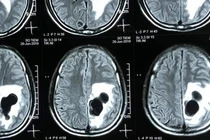

| Hình ảnh CT sọ não phát hiện tổ sán lợn trong não bệnh nhân |

Liệt nửa người, não có 5 tổ sán do món "khoái khẩu" tiết canh

Do ăn tiết canh, một người đàn ông ở huyện Quỳ Hợp, Nghệ An đã bị liệt nửa người vì não có nhiều sán làm tổ gây phù não.